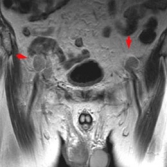

- atteinte du bassin, du rachis